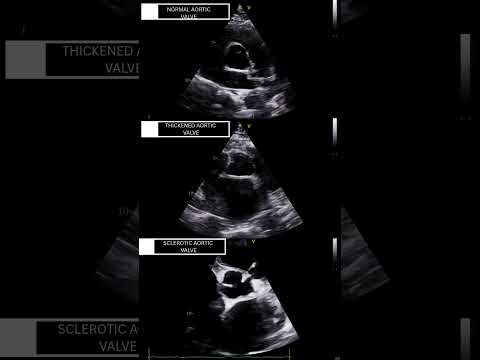

Aortic Valve – Normal vs Thickened vs Sclerosed (2D TTE) #echocardiography #2decho #echoeducation